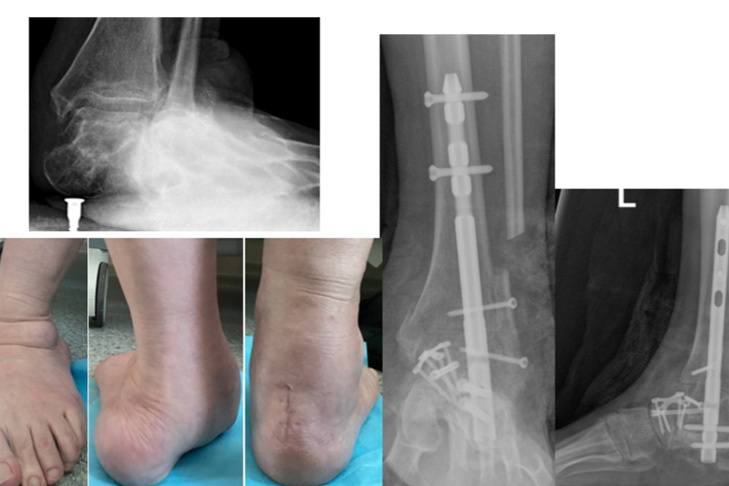

Фото НИИТО им. Я.Л. Цивьяна

«Я встану на ноги и пойду»: так описывает свои планы Ирина Чубич, преподавательница из Новосибирска, которой в НИИТО им. Я.Л. Цивьяна провели реконструктивные операции при тяжёлой плосковальгусной деформации обеих стоп.

По данным травматолого‑ортопедического отделения №6, у пациентки была запущенная форма деформации: стопы смещались внутрь, суставы имели патологические соотношения. Ранее применяли консервативные методы — ортопедическую обувь и стельки, однако на этой стадии изменения стали анатомическими, и без хирургии восстановить правильное положение костей было невозможно.

В НИИТО выполнили реконструктивную операцию с восстановлением соотношения костей и фиксацией специальными конструкциями для срастания в правильной позиции. Завотделением, к.м.н. Сергей Гуди, пояснил стандартную схему лечения: «Сначала мы оперируем более поражённую ногу: таков стандарт безопасности. Затем требуется хирургическая пауза, чтобы пациентка восстановилась, научилась ходить на костылях, опираясь на здоровую ногу. Только когда первая стопа уже может служить надёжной опорой, мы оперируем вторую».

По словам врачей, это минимизирует риски и делает реабилитацию комфортнее. В обоих случаях выполняется реконструктивная операция: мы вернули стопе правильное положение и зафиксировали кости при помощи специальных конструкций, чтобы они срослись в нужной позиции.